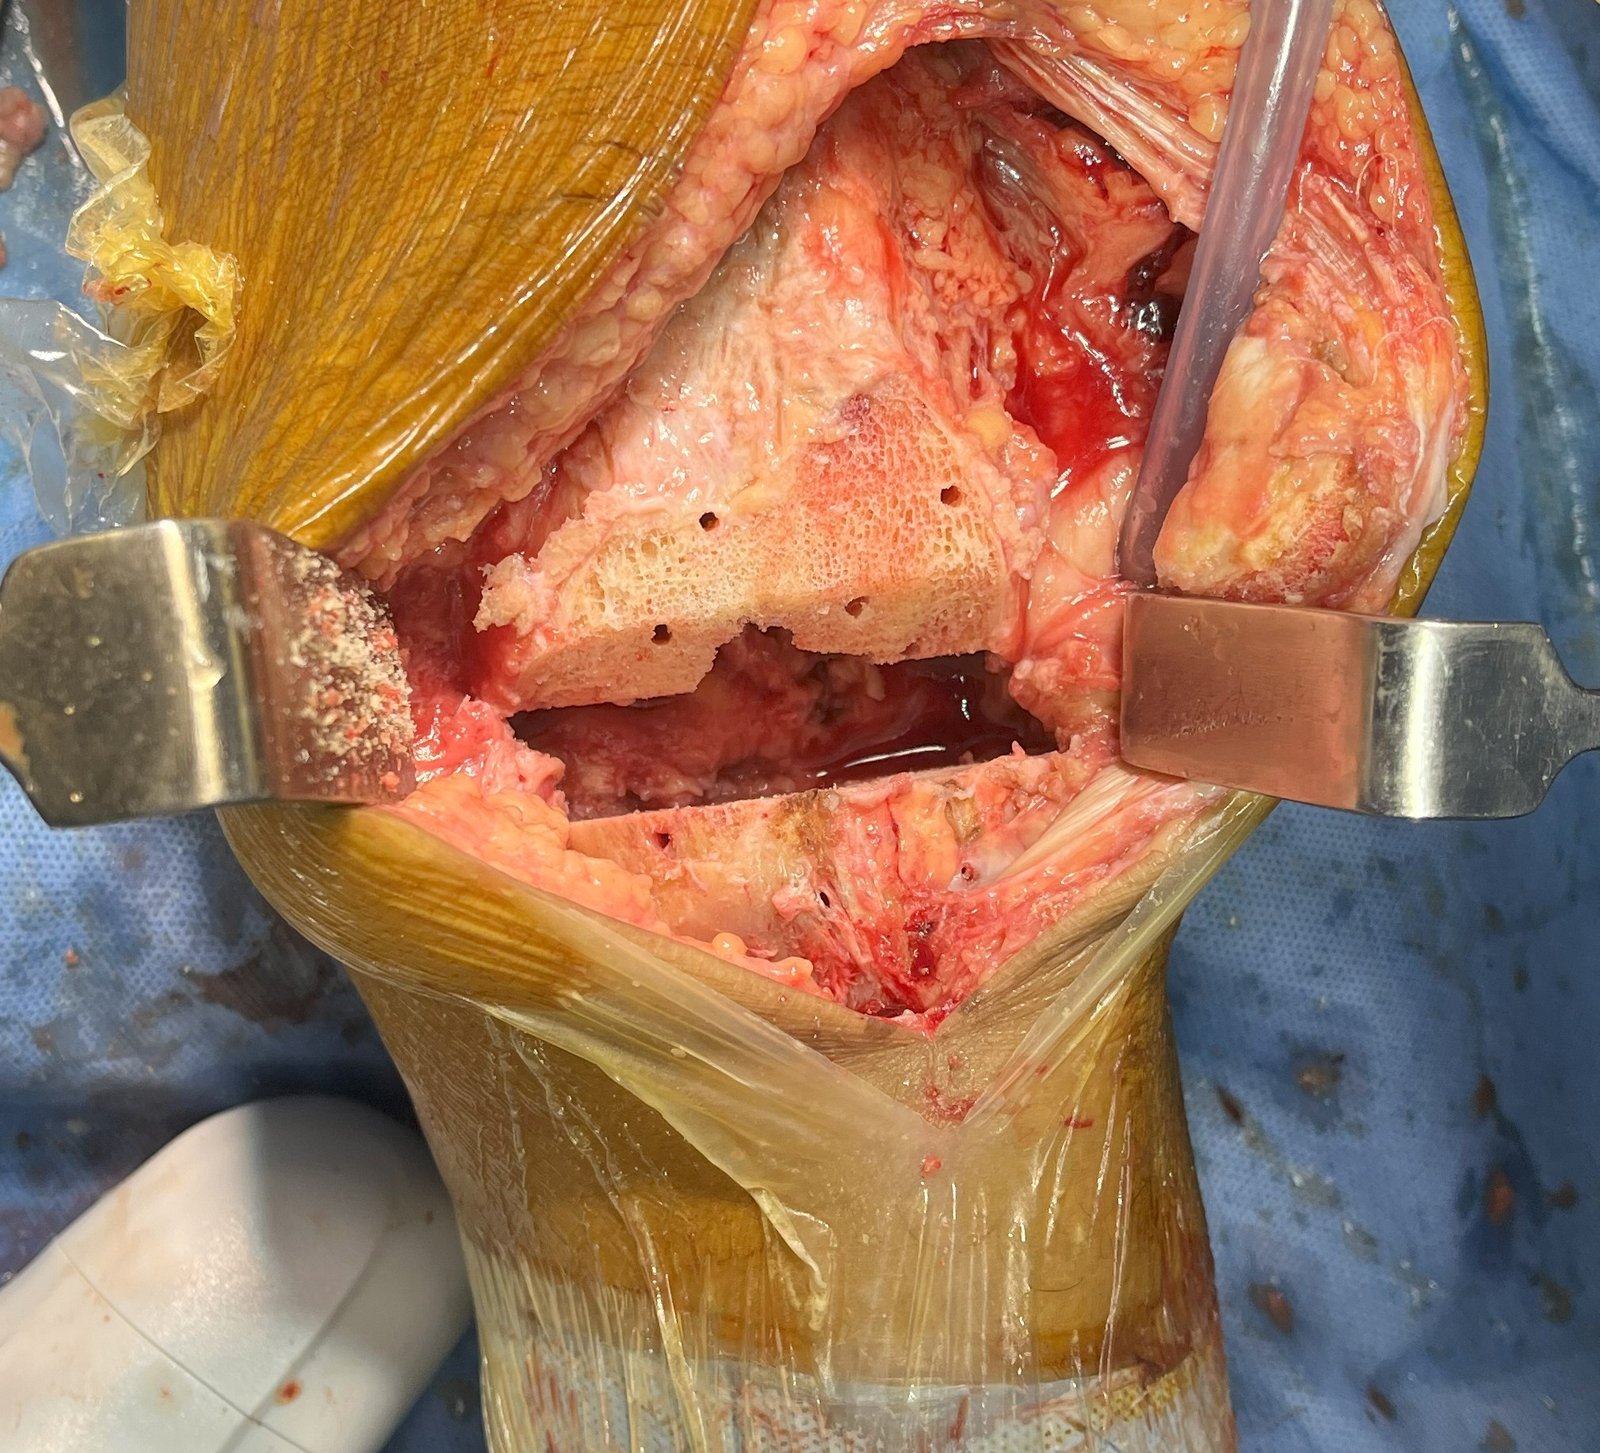

Intra-Op (Photos)

Post DFC Cut

Tibial Cut

APCC Cut

Prior Cementation Cocktail Infiltration

Cementation Tibial Tray

DFC & Tibial Cut